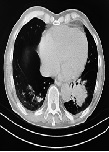

Extended Progression-Free Survival of Renal Cell Carcinoma with Axitinib: Case Report